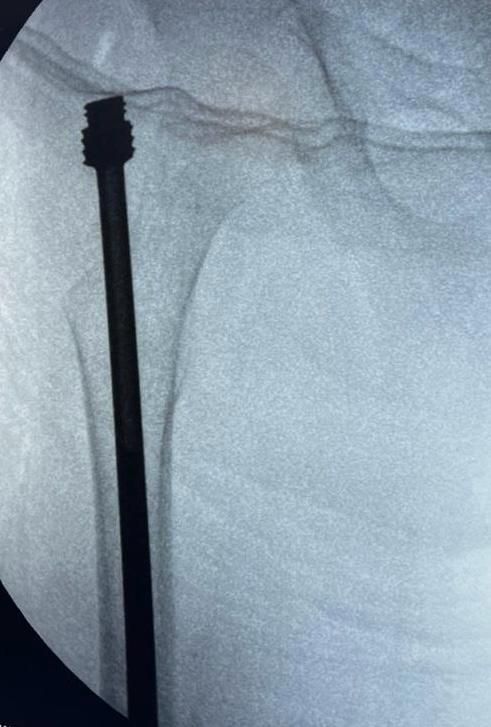

Cada caso es valorado a profundidad para proponer tratamientos conservadores (rehabilitación, ejercicios, ortesis) o procedimientos quirúrgicos cuando son necesarios, como artroplastías (colocación de prótesis articulares) o cirugías mínimamente invasivas como la artroscopía.